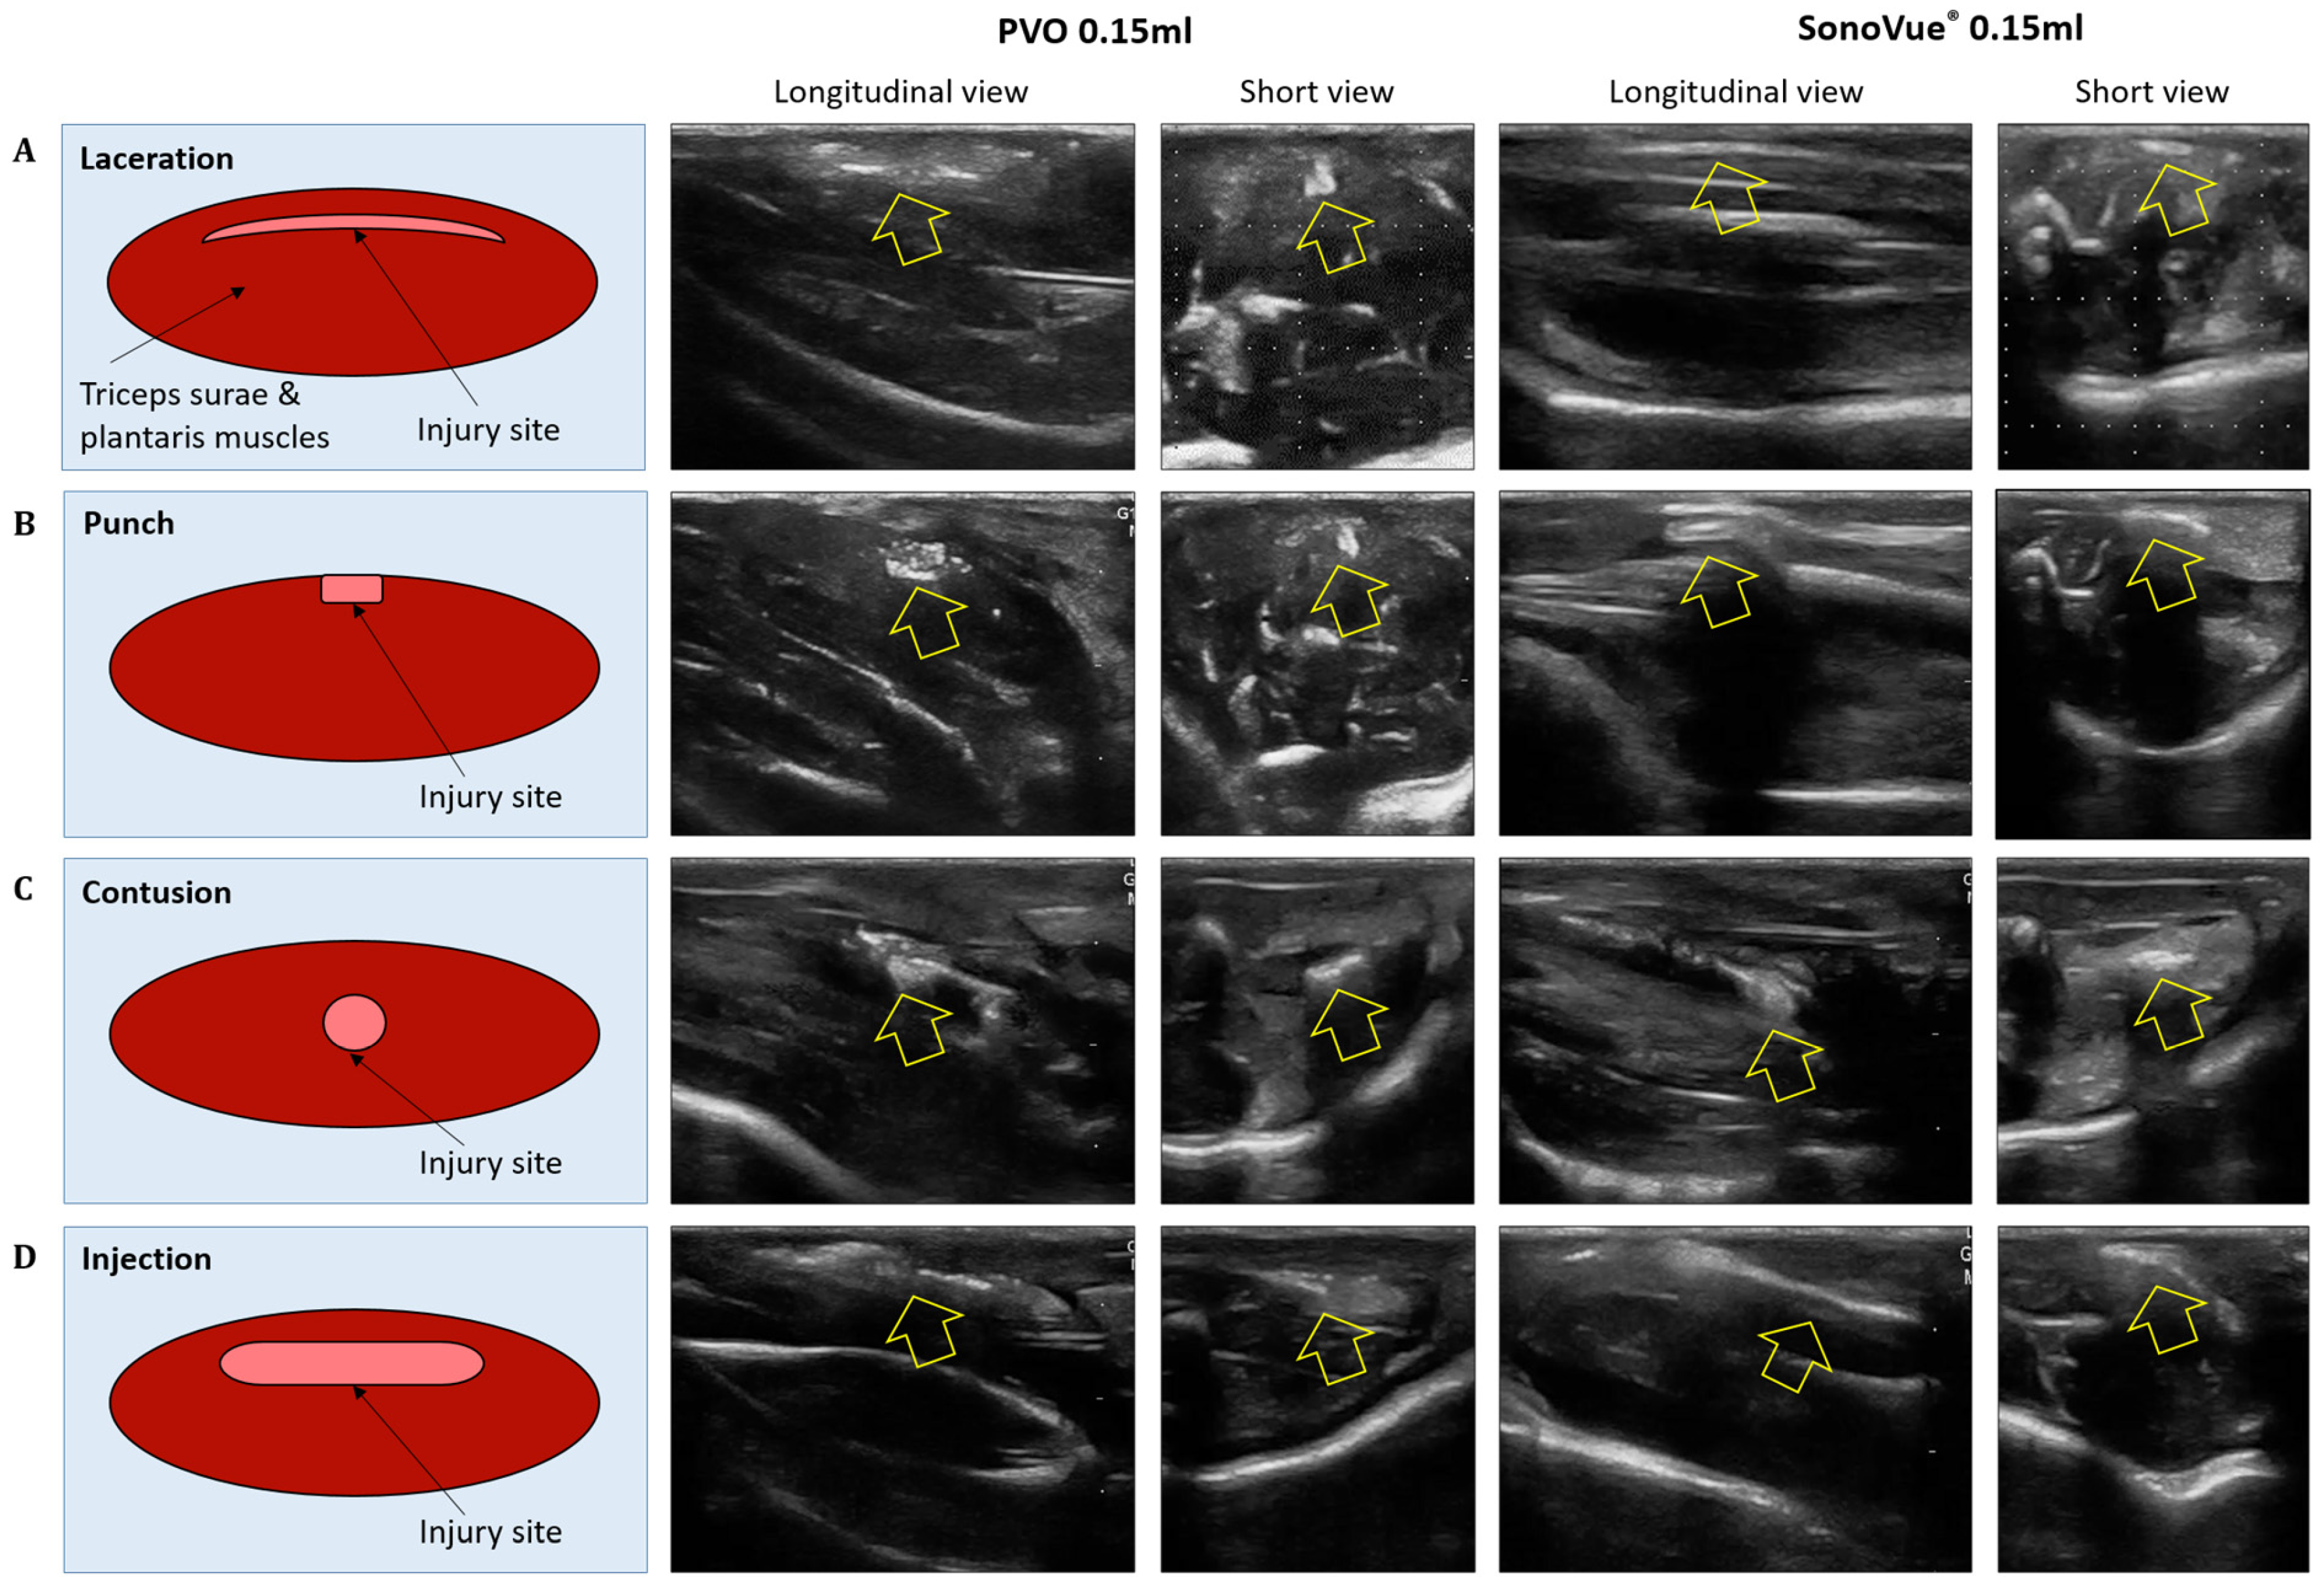

3.3. Ultrasound Images after PVO and SonoVue® Injection in the Muscle Injured Models

3.3.1. Laceration Model

3.3.2. Punch Models

3.3.3. Contusion Models

3.3.4. Toxin Injection Models